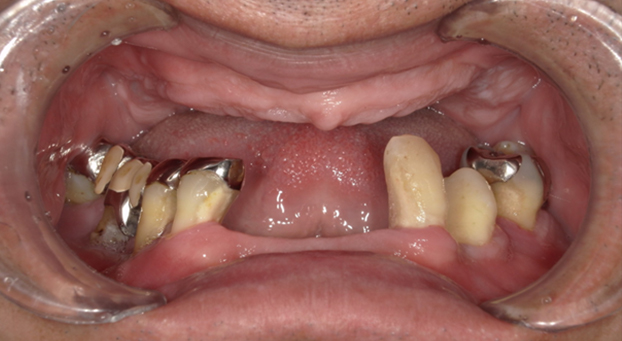

インプラント治療では、歯を失くした部分にインプラント体と呼ばれる人工の歯の根と人工の歯を装着し、失った歯の機能を取り戻すことを目指します。入れ歯やブリッジとは異なり、周りの健康な歯を削ったり、負担をかけたりする心配がなく、審美性にも優れた自由診療の治療です。これらの他にも多くのメリットがあります。

インプラント治療を行った歯は、自然な見た目が特徴です。入れ歯などとは異なり、周囲に気づかれる心配はほとんどありません。

インプラント治療は、入れ歯についてのさまざまなお悩みの改善に役立つ治療法です。